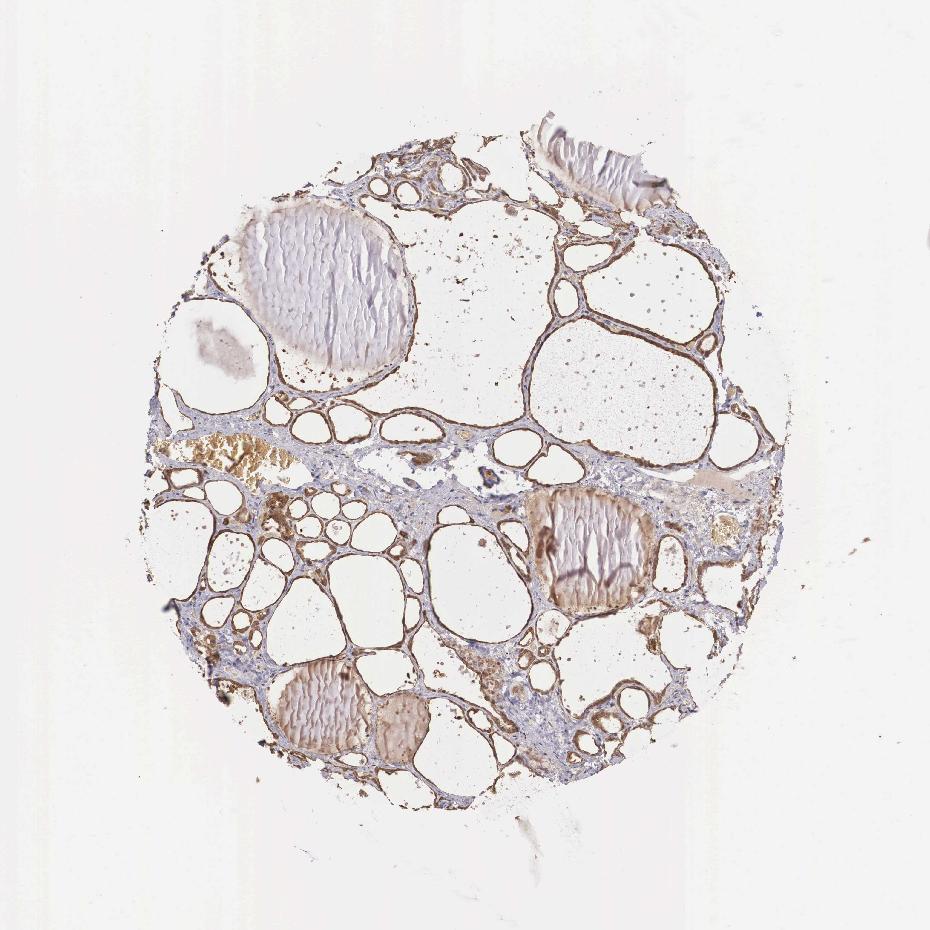

THYROID GLAND - Antibody stainingi

Antibody staining in the annotated cell types in the current human tissue is reported as not detected, low, medium, or high, based on conventional immunohistochemistry profiling in selected tissues. This score is based on the combination of the staining intensity and fraction of stained cells.

Each image is clickable and will lead to virtual microscopy that enables deeper exploration of all samples and also displays staining intensity scores, fraction scores and subcellular localization as well as patient and tissue information for each sample.

Antibody HPA000653

Glandular cells Medium